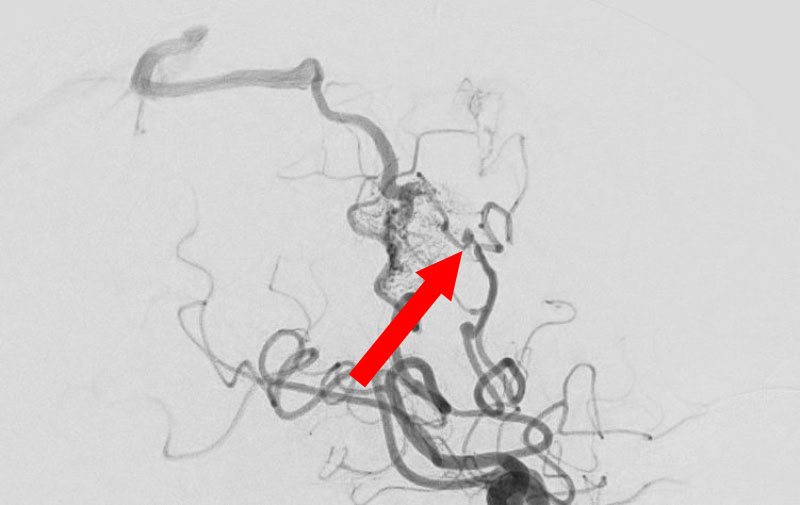

'25年10月

脳動静脈奇形

50代

大阪府の病院

No.1585 手術前

No.1585 手術中

No.1585 手術後